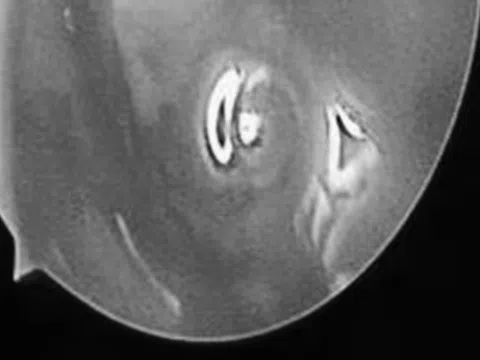

Kết quả chụp cộng hưởng từ (MRI) sọ não cho thấy một tổn thương dạng nang nhỏ tại thùy trán trái, kích thước khoảng 11 x 7 mm, xung quanh có phù não nhẹ. Hình ảnh này gợi ý nhiều đến tổn thương do ký sinh trùng hơn là u não nguyên phát.

Hình ảnh chụp chiếu trước và sau khi điều trị (Ảnh: BVCC).

Khi tái khám gần một tháng sau, phim MRI cho thấy tổn thương não thu nhỏ rõ rệt, phù não giảm, không còn dấu hiệu tiến triển, chứng tỏ đáp ứng điều trị tốt. Bệnh nhân được chỉ định thêm một đợt thuốc củng cố và theo dõi lâu dài.